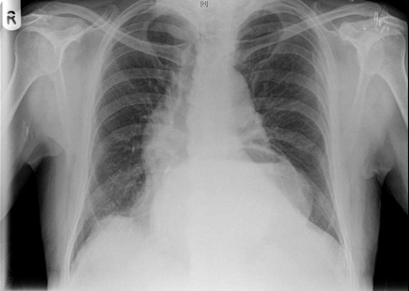

A 73-year-old male presented to the emergency department with a one-day history of severe epigastric pain with vomiting progressing to dry retching. He admitted to a long history of esophageal reflux symptoms treated with oral omeprazole. His initial examination revealed a tachycardia and a swollen, tender epigastrium but no other signs of note. A nasogastric tube was passed with difficulty, he was made nil by mouth and treated with intravenous crystalloids. Laboratory blood results were unremarkable including normal amylase and liver function tests. A chest X-ray showed a large retrocardiac viscus reported as a large hiatus hernia while his abdominal film demonstrated a paucity of bowel gas (Figure 1). An abdominal and thoracic computed tomography (CT) scan revealed a moderate hiatus hernia without obvious perforation and the possible appearance of a rotational component of the stomach with dilatation to the pylorus and no fluid beyond this point. A subsequent upper gastrointestinal contrast study clearly demonstrated an 'upside-down stomach' sign and established the diagnosis of an obstructing organoaxial volvulus secondary to a paraesophageal hiatus hernia (Figure 2) [1]. On transfer to our facility the patient went on to have definitive laparoscopic gastropexy surgery involving reduction of the volvulus, excision of the hernia sac, re-approximation of the diaphragmatic crura then placement of four sutures anchoring the greater curvature of the stomach to the abdominal wall. He has had no recurrence of the volvulus and was symptom free when followed-up in clinic for six months. | ||||||

Gastric volvulus is an abnormal rotation of the stomach through more than 180 degrees, first described by Berti in 1866 [2]. This can lead to ulceration, perforation, hemorrhage, ischemia or necrosis [1]. The non-operative mortality rate is as high as 80% [3]. Adults with acute gastric volvulus typically present with epigastric pain and distension, unproductive vomiting and difficulty with nasogastric tube insertion. A constellation known as Borchardt's triad [4]. About 10–20% of cases occur in children, in adults it can occur at any age but is more common after the fourth decade of life [1] [5] . Gastric volvulus can be classified according to the axis around which the stomach rotates. In organoaxial volvulus, the stomach rotates around an axis connecting the gastroesophageal junction with the pylorus. This is the most common type of gastric volvulus occurring in approximately 60% of cases and commonly leads to strangulation and necrosis [6]. In mesenteroaxial volvulus, there is a transverse axis and the antrum rotates antero-superiorly so that the posterior surface of the stomach lies anteriorly. It is also possible to have a combined type volvulus. The most common causes of gastric volvulus in adults are diaphragmatic defects. In the case of paraesophageal hernia related volvulus, as we report, the gastroesophageal junction remains in the abdomen, whereas the stomach ascends adjacent to the esophagus, resulting in a horizontally lying, upside down stomach [2]. X-ray appearances include a retrocardiac gas/fluid filled viscus on chest film if the stomach is in the thorax and a paucity of distal gas on plain abdominal film [7]. Several authors recommend computed tomography imaging as the diagnostic method of choice, this may show a torted bi-lobular stomach with a transition line [2] [8] [9]. However, the diagnosis of gastric volvulus is classically based on upper gastrointestinal contrast studies using barium or Gastrografin. These studies are both sensitive and specific if performed in the twisted state and classically show an upside-down stomach' sign as well as illustrating the degree of obstruction [8]. Endoscopic reduction of gastric volvuli is possible but recurrence rates are high if this is performed as an isolated procedure [2]. Surgical repair was traditionally based on an open approach but this has been superseded by modern minimally invasive techniques. Laparoscopic suture gastropexy, as described in our case, is safe and effective for both acute and chronic gastric volvulus [1] [2] [3] . | ||||||